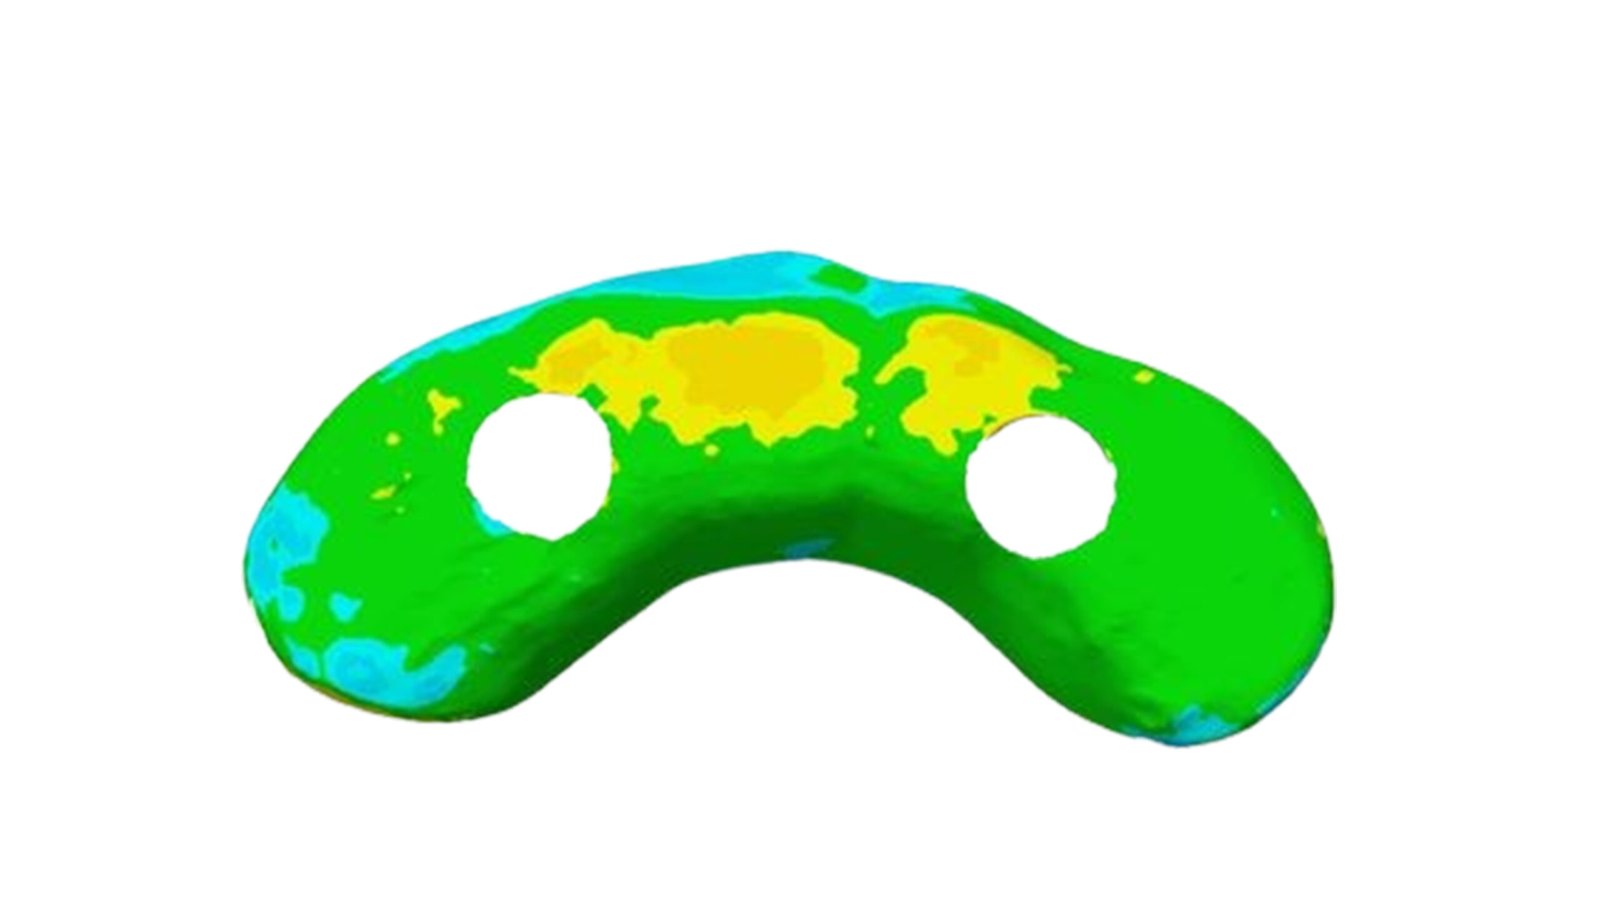

This section specializes in high-precision 3D deviation mapping to compare pre- and post-treatment anatomical or implant-related geometries. Using advanced superimposition and deviation algorithms, we quantify micro-level shifts, deformation zones, and structural discrepancies with sub-millimeter accuracy. These analyses support quality control, surgical verification, and design validation. The resulting deviation heat-maps provide clear, data-driven insights that enhance clinical decision-making and device optimization.